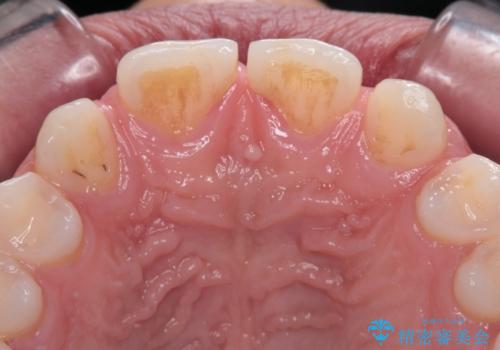

欠損して隙間のある前歯 オールセラミッククラウンで自然な口元に

- 歯の欠損による前歯のすきっ歯を気にして来院された患者様です。

矯正治療かオールセラミックか、治療の選択がありましたが、熟考の末オールセラミッククラウンにて補綴することとしました。